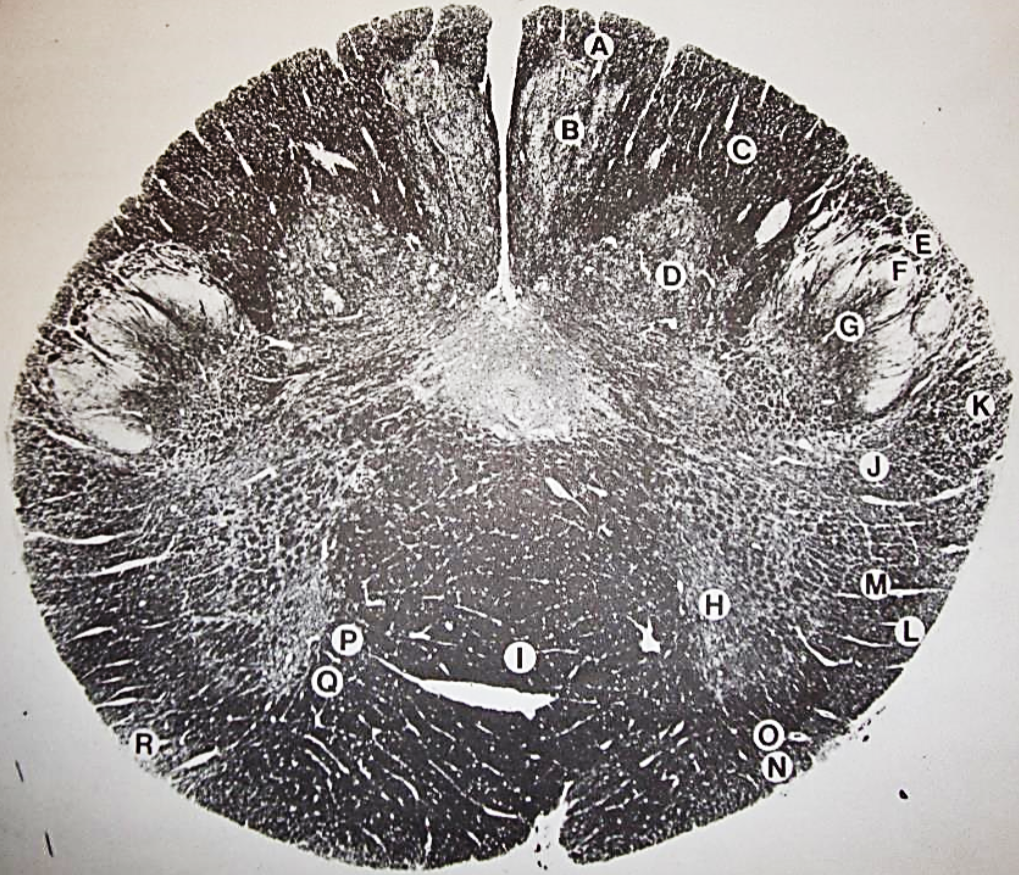

A

fasciculus gracilis

B

gracile nucleus

C

fasciculus cuneatus

D

cuneate nucleus

F

internal arcuate fibers

G

decussation of internal arcuate fibers

H

medial lemniscus

I

hypoglossal nucleus

J

dorsal motor nucleus vagus

K

solitary fasciculus

L

solitary nucleus

M

dorsal longitudinal fasciculus

N

spinal trigeminal tract

O

spinal trigeminal nucleus

P

posterior spinocerebellar tract

Q

anterior spinocerebellar tract

R

spinal lemniscus

S

lateral vestibulospinal tract

T

rubrospinal tract

U

lateral reticular nucleus

V

medial accessary olivary nucleus

W

pyramidal (corticospinal) tract

X

arcuate nucelus

Y

medial longitudinal fasciculus

Z

tectospinal tract

a

fascicles of hypoglossal nerve